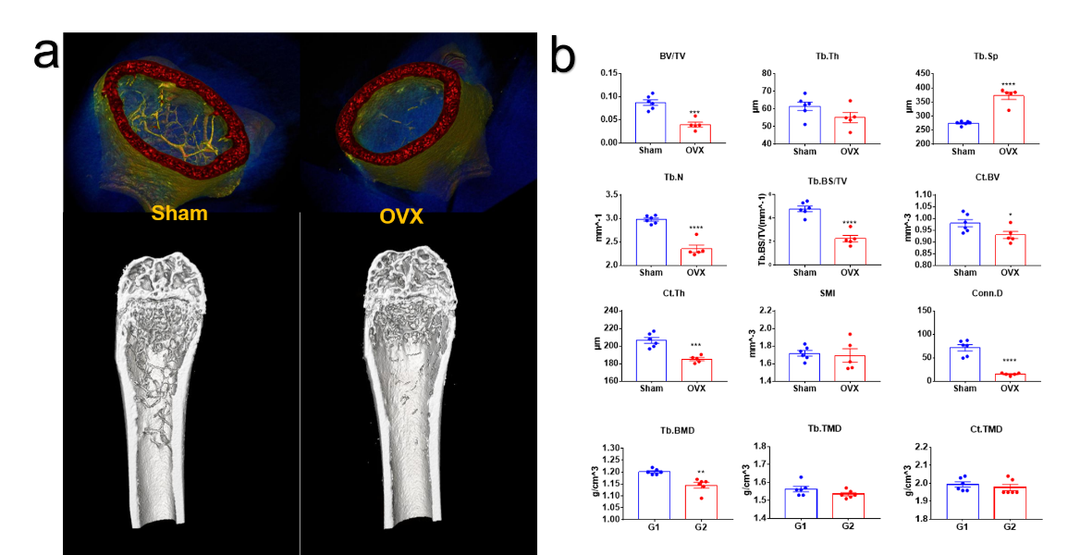

骨质疏松小鼠模型 (Ex/In vivo)-密度属性、结构性参数

卵巢切除诱导的骨质疏松模型离体检测。(a)骨质疏松模型假手术组(sham)和手术组(OVX)3D重建图像。(b)骨小梁、皮质骨结构性参数以及密度属性参数统计图。指标意义参考下方表格,综上结果模型特征明显,手术成功。

骨分析常见参数的意义